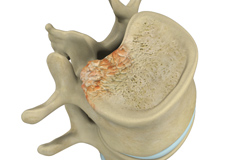

Vertebral Compression Fractures

Back pain is an indication of stress fractures known as vertebral compression fractures. Vertebral compression fractures occur when the normal vertebral body of the spine is squeezed or compressed. The bone collapses when too much pressure is placed on the vertebrae, resulting in pain, limited mobility, loss of height and spinal deformity.

Osteoporosis of the Spine

Osteoporosis is a bone disease characterized by a decrease in bone mass and density resulting in brittle, fragile bones that are more susceptible to fractures. The condition most commonly affects elderly women. Osteoporosis-related fractures are more common at the vertebral bodies of the spine.